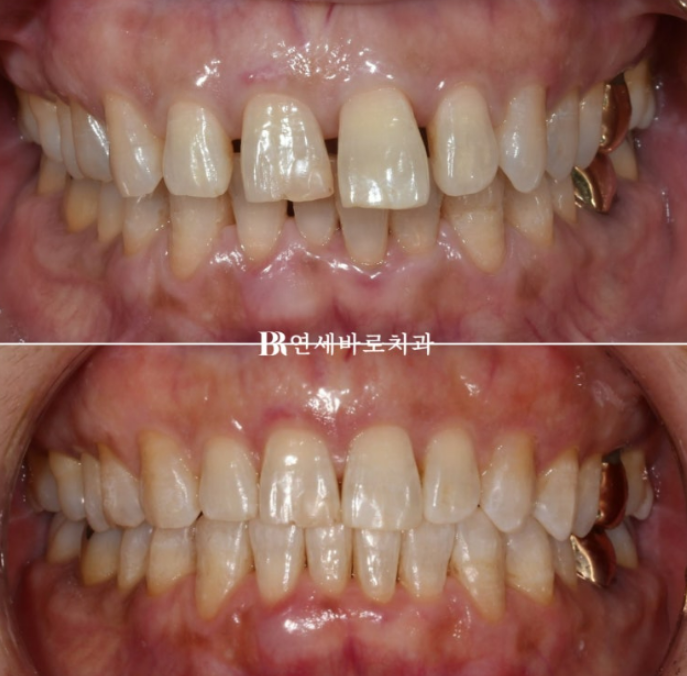

6개월 간 치료 후 마무리 하였습니다.

인비절라인 1차로 치료가 끝난 후 디테일한 부분들을 수정하는 추가장치를 제작해야 하는 경우가 많은데 워낙에 장치를 잘 껴주셨고 치아 이동도 원활한 편이어서 추가장치 없이 마무리 했습니다.

교정이 너무 빨리 끝났다며 아쉬워 하셨습니다.

점점 벌어지면서 돌출 되었던 앞니가 다시 뒤로 들어가며 제자리를 찾았습니다.

적절한 치료 계획, 적당한 갯수의 올바른 어태치먼트의 배치 각 치아 마다 다른 전략적인 staging 자잘한 노하우들이 쌓여 가장 빠르고 좋은 결과를 만들어 냅니다.